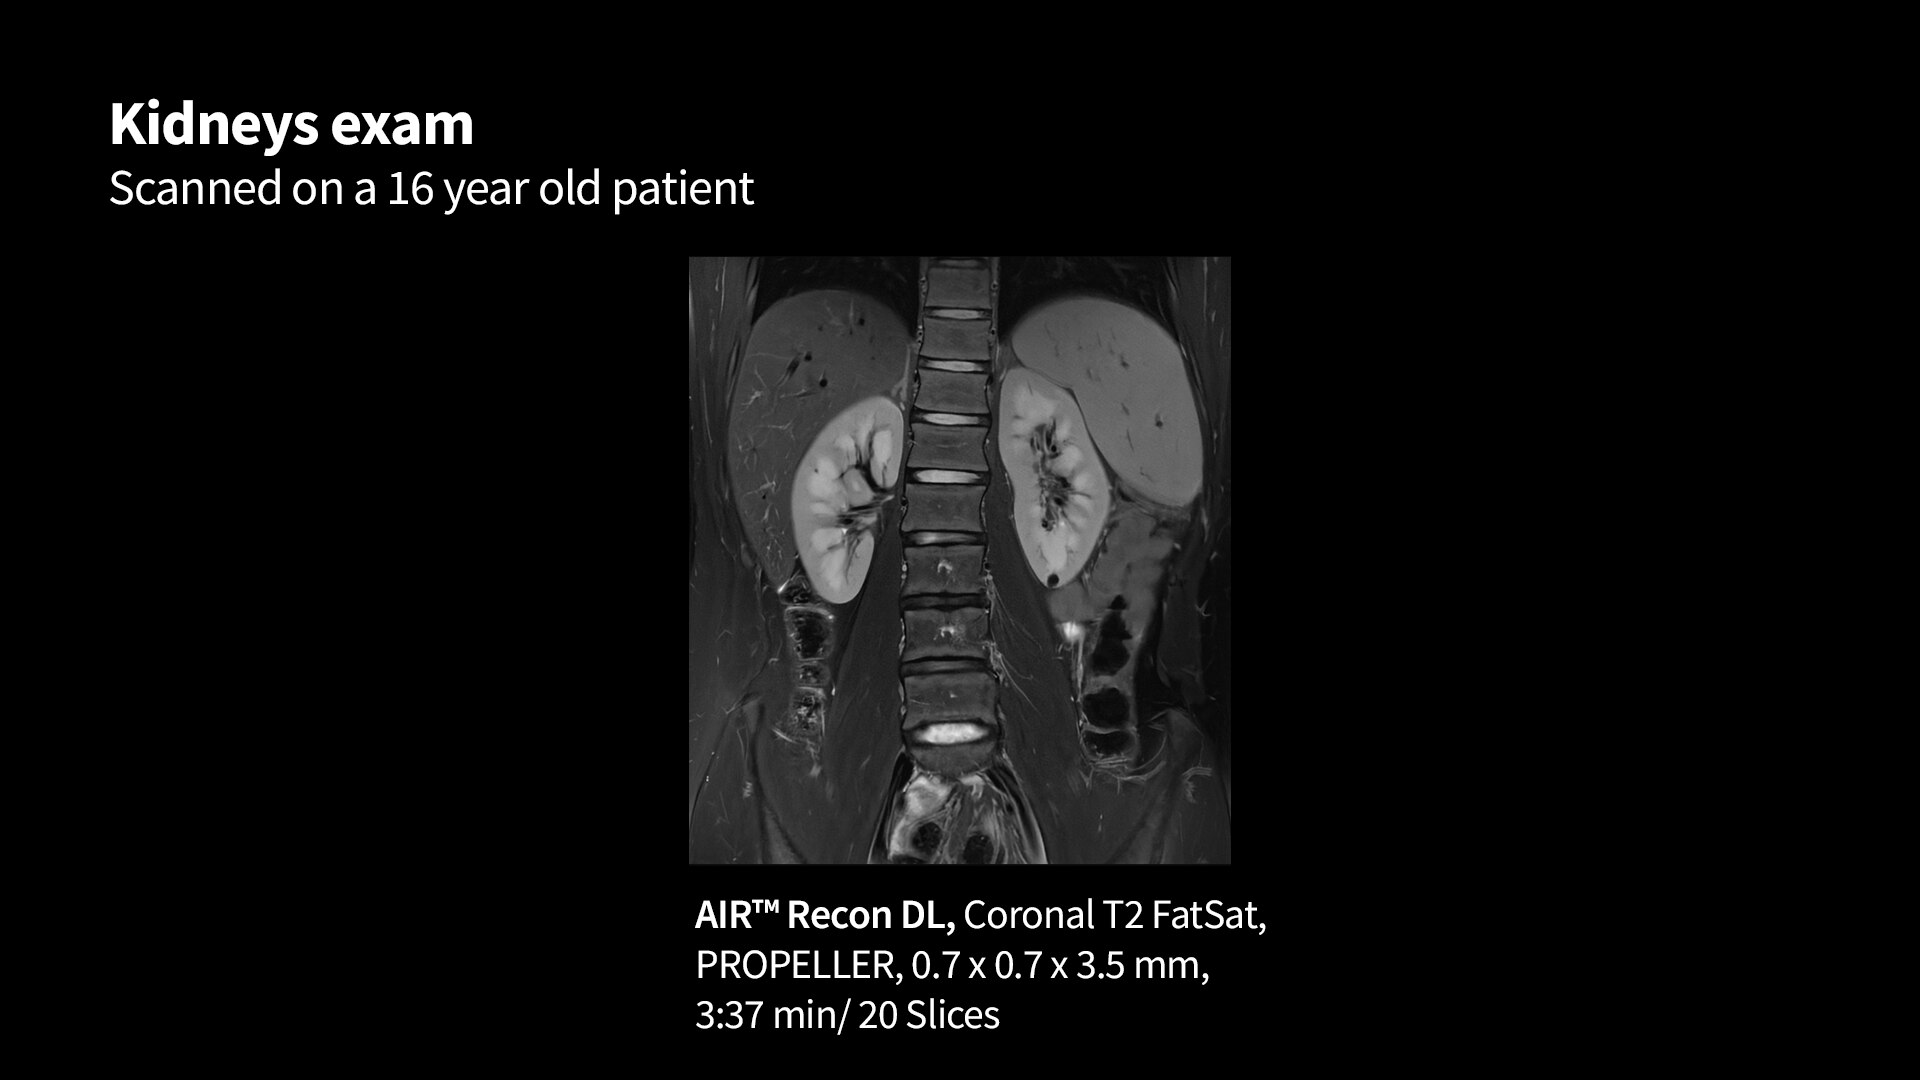

MR image reconstruction with AIR™ Recon DL

AIR™ Recon DL has revolutionized MR imaging with deep-learning based image reconstruction increased image quality, reduced scan time and improved SNR.